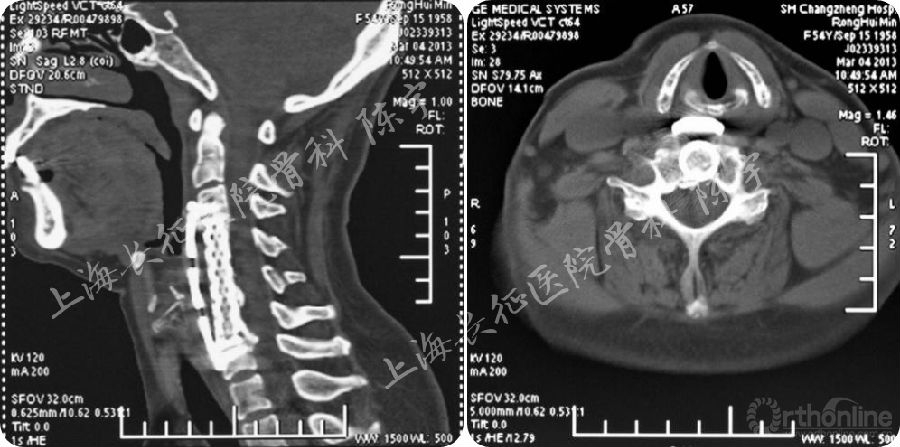

术后影像学检查(图2):

(1) X线:显示颈前路C4-6椎体次全切除减压钛网植骨融合术;

(2) MRI:显示术后脊髓减压充分,脊髓形态完全恢复;

(3) CT: 显示后纵韧带骨化物完全切除,硬膜囊骨化保留并向前漂移。